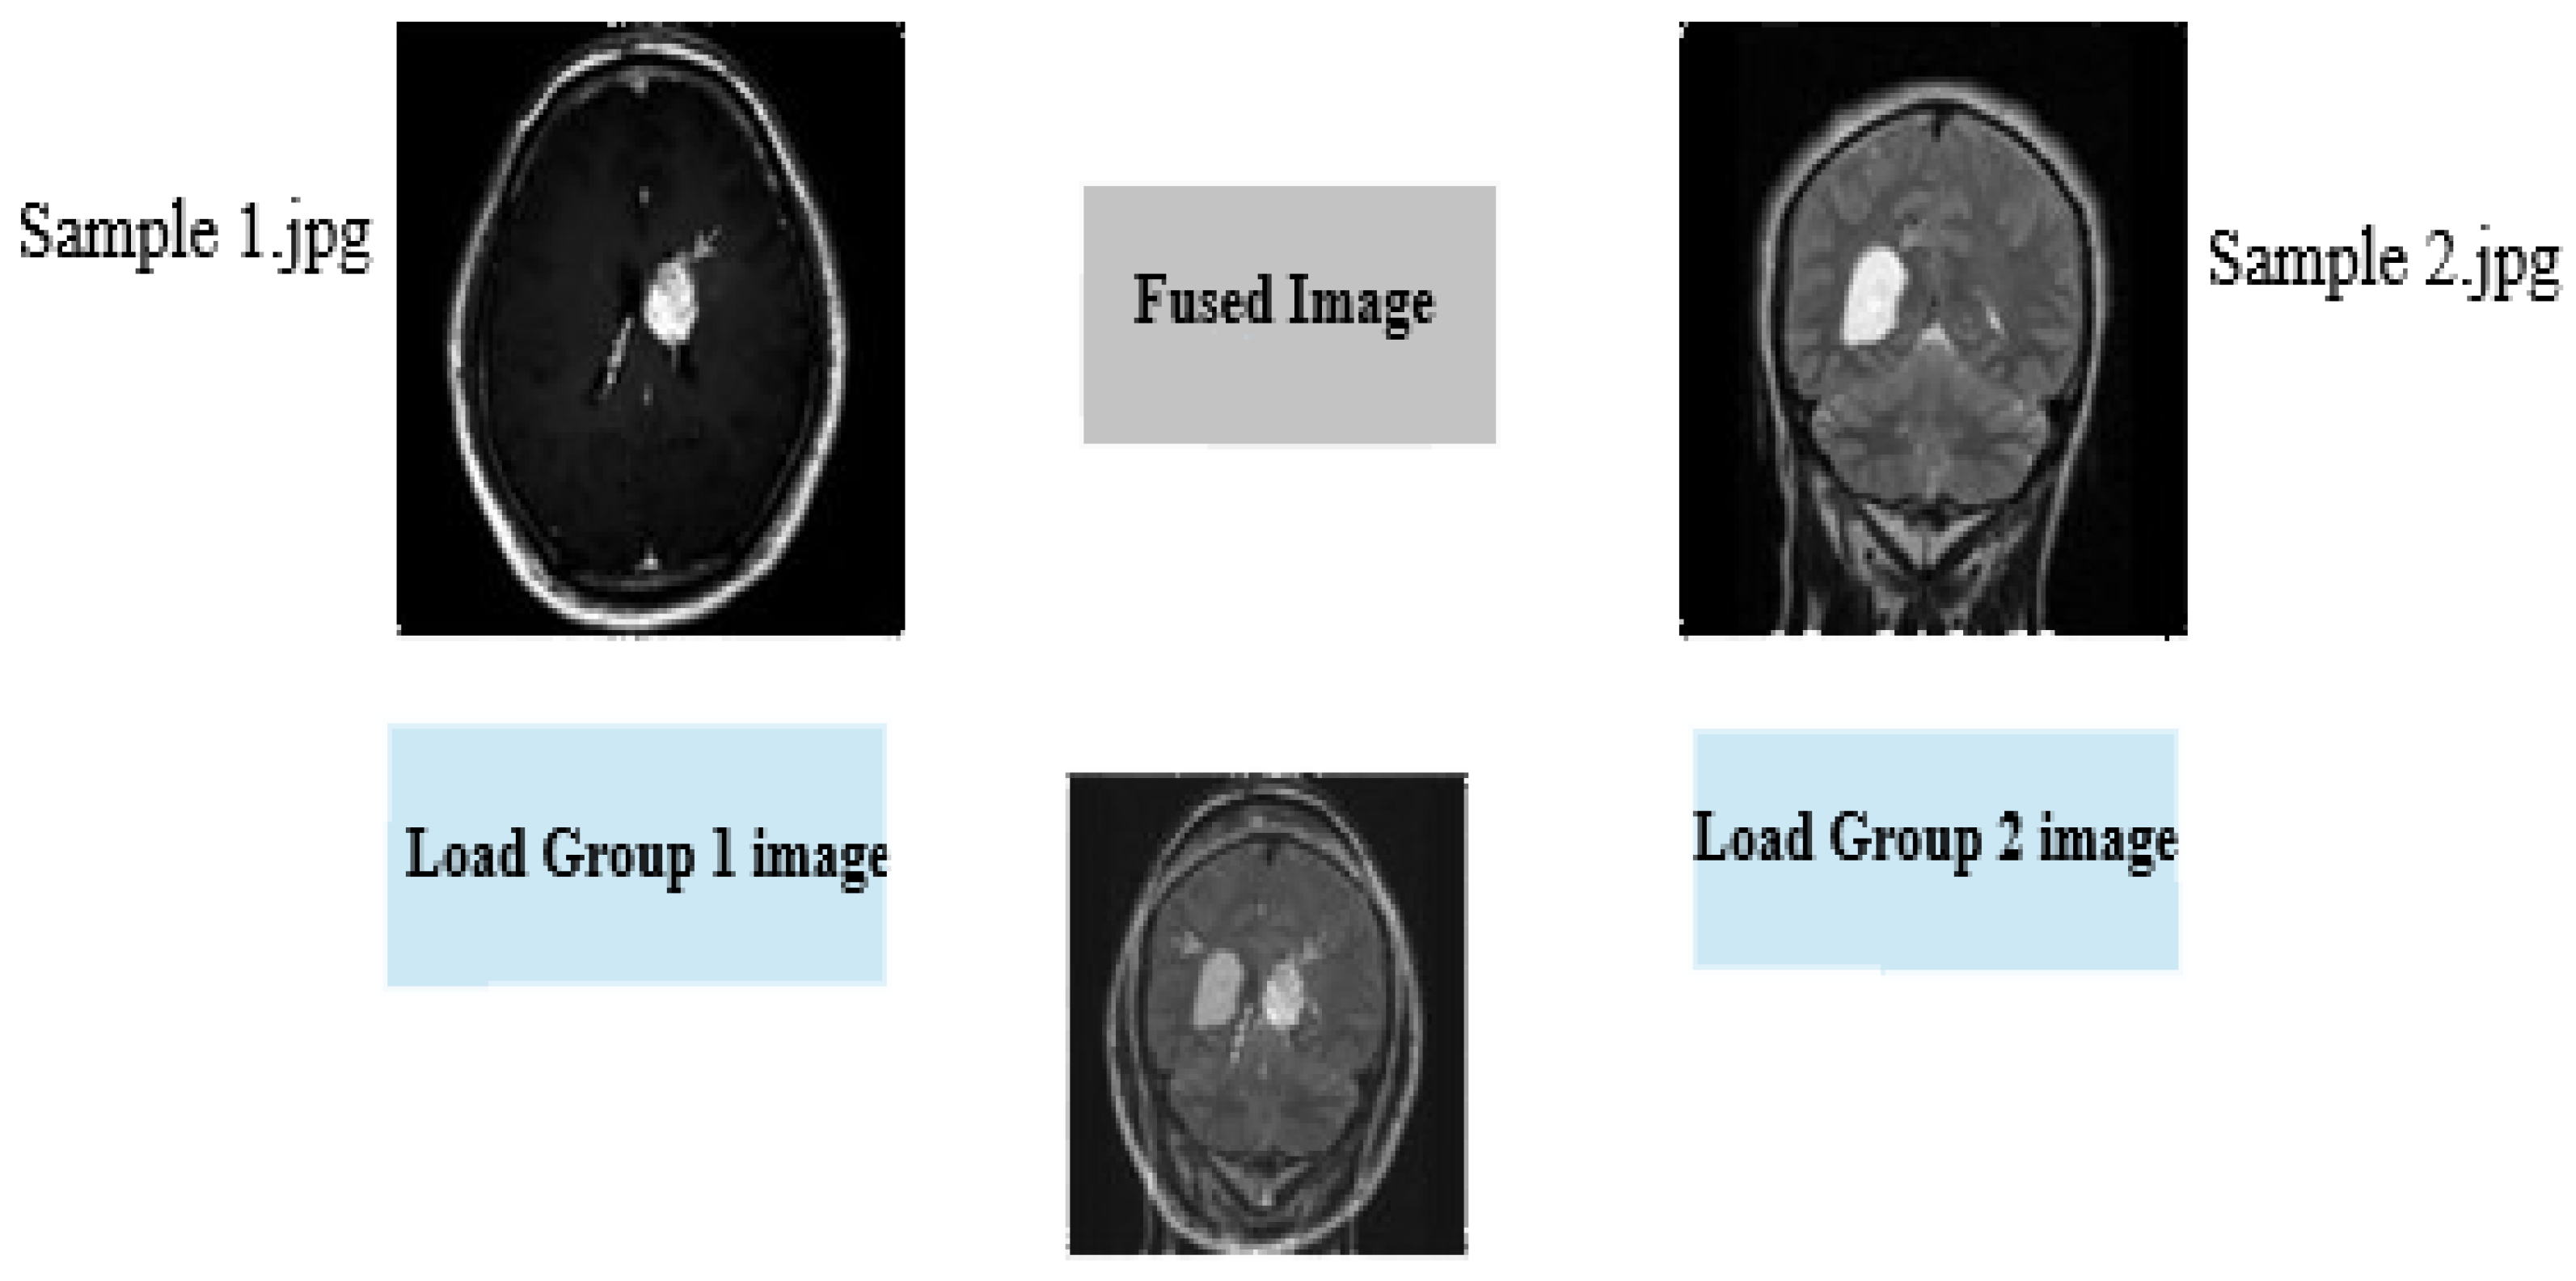

Figure 8. The fused image in the third axis.

Information 15 00612 g008